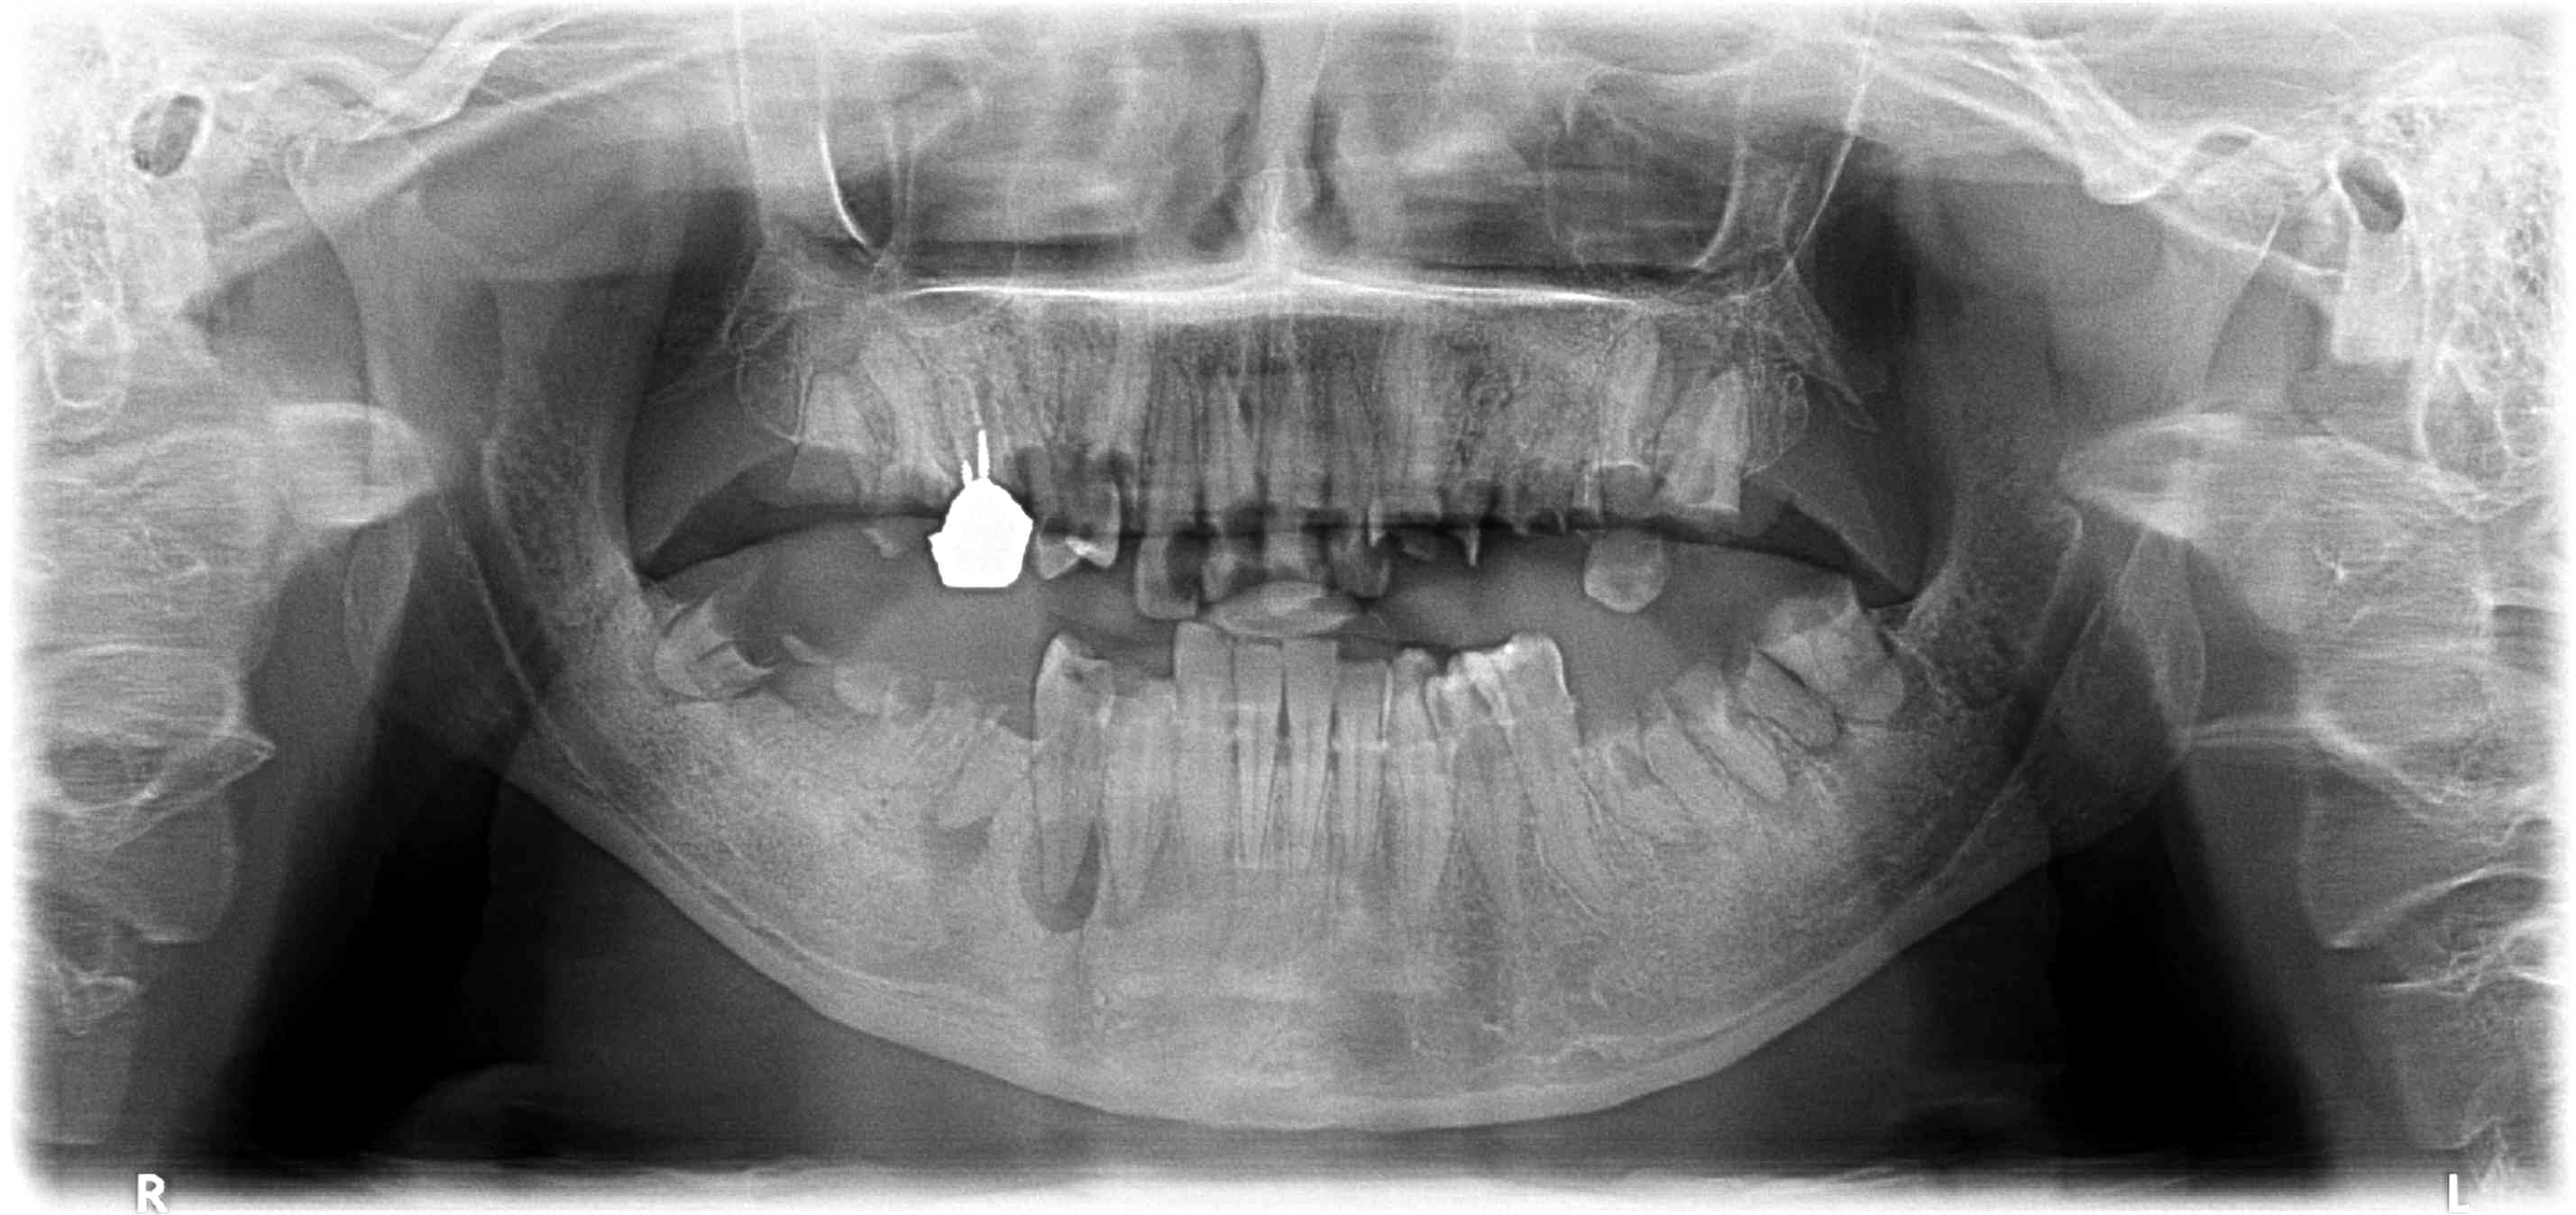

radiographies CAT

Capture d  cran 2015 03 12 12.28 - Eugenol

Ici on a du 2 du 3 en film agrémentés de quelques clichés de capteur RVG taille 1. -)

On va mélanger le nombre de radios, les formats et le nombre de secteurs pour noyer le poisson. Il y a une multitude d'emplacement libres sur mon FMS tuné. -)